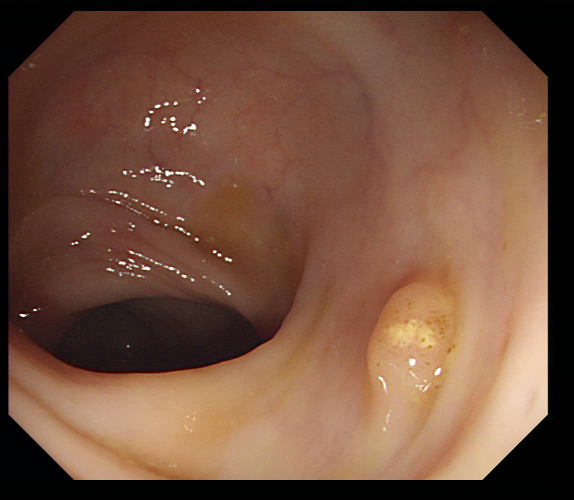

Early polyp segmentation was based in the texture and shape of the polyps. For example, Hwang et al. [8] used ellipse fitting techniques based on shape. However, some corectal polyps can be small (5mm) and are not detected by these techniques. In addition, the texture is easily confused with other tissues in the colon as can be seen in Figure 2.

With the rise of convolutional neural networks (CNNs) [10] the problem of the texture and shape of the polyps was solved and the accuracy was substantially increased. Several authors have applied deep convolutional networks to the polyp segmentation problem. Brandao et al. [2] proposed to use a fully convolutional neural network based on the VGG [16] architecture to identify and segment polyps. Unfortunately, the small datasets available and the large number of parameters make these large networks prone to overfitting. Zhou et al. [22] used an encoder-decoder network with dense skip pathways between layers that prevented the vanishing gradient problem of VGG networks. They also significantly reduced the number of parameters, reducing the amount of overfitting. More recently, Chao et al. [3] reduced the number of shortcut connections in the network to speed-up inference time, a critical issue when performing real-time colonoscopies in high-resolution. They focused on reducing the memory traffic to access intermediate features, reducing the latency. Finally, Huang et al. [7] improved the performance and inference time by combining HarDNet [3] with a cascaded partial decoder [21] that discards larger resolution features of shallower layers to reduce latency.